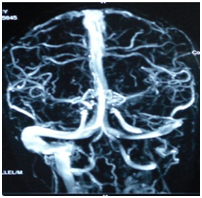

Patient was admitted and started on empirical intravenous antibiotics. Mantoux test was negative. An attempt of lumbar puncture was unsuccessful. High Resolution Computed Tomography of temporal bone was suggestive of an ill defines iso-dense heterogeneously enhancing lytic expansile lesion involving left jugular bulb causing erosion of squamous part of temporal bone, clivus, mastoid part of temporal bone with thrombosis of left sigmoid sinus and internal jugular vein (Figure 1). Post contrast Magnetic Resonance Imaging of brain revealed an ill-defined moderately heterogeneous enhancing lesion of left jugular bulb causing erosion of squamous part of occipital bone and extending into pre and para vertebral space up to level of C1 vertebra and causing destruction of mastoid part of temporal bone with thrombosis of left sigmoid sinus and internal jugular vein (Figure 2). Cranial Magnetic Resonance Imaging venography showed thrombosis in left sigmoid sinus and internal jugular vein (Figure 3). Blood investigations ruled out the presence of hypercoagulable state in our patient.

Figure 3 Cranial Magnetic Resonance Imaging Venography: Absent flow in left side.